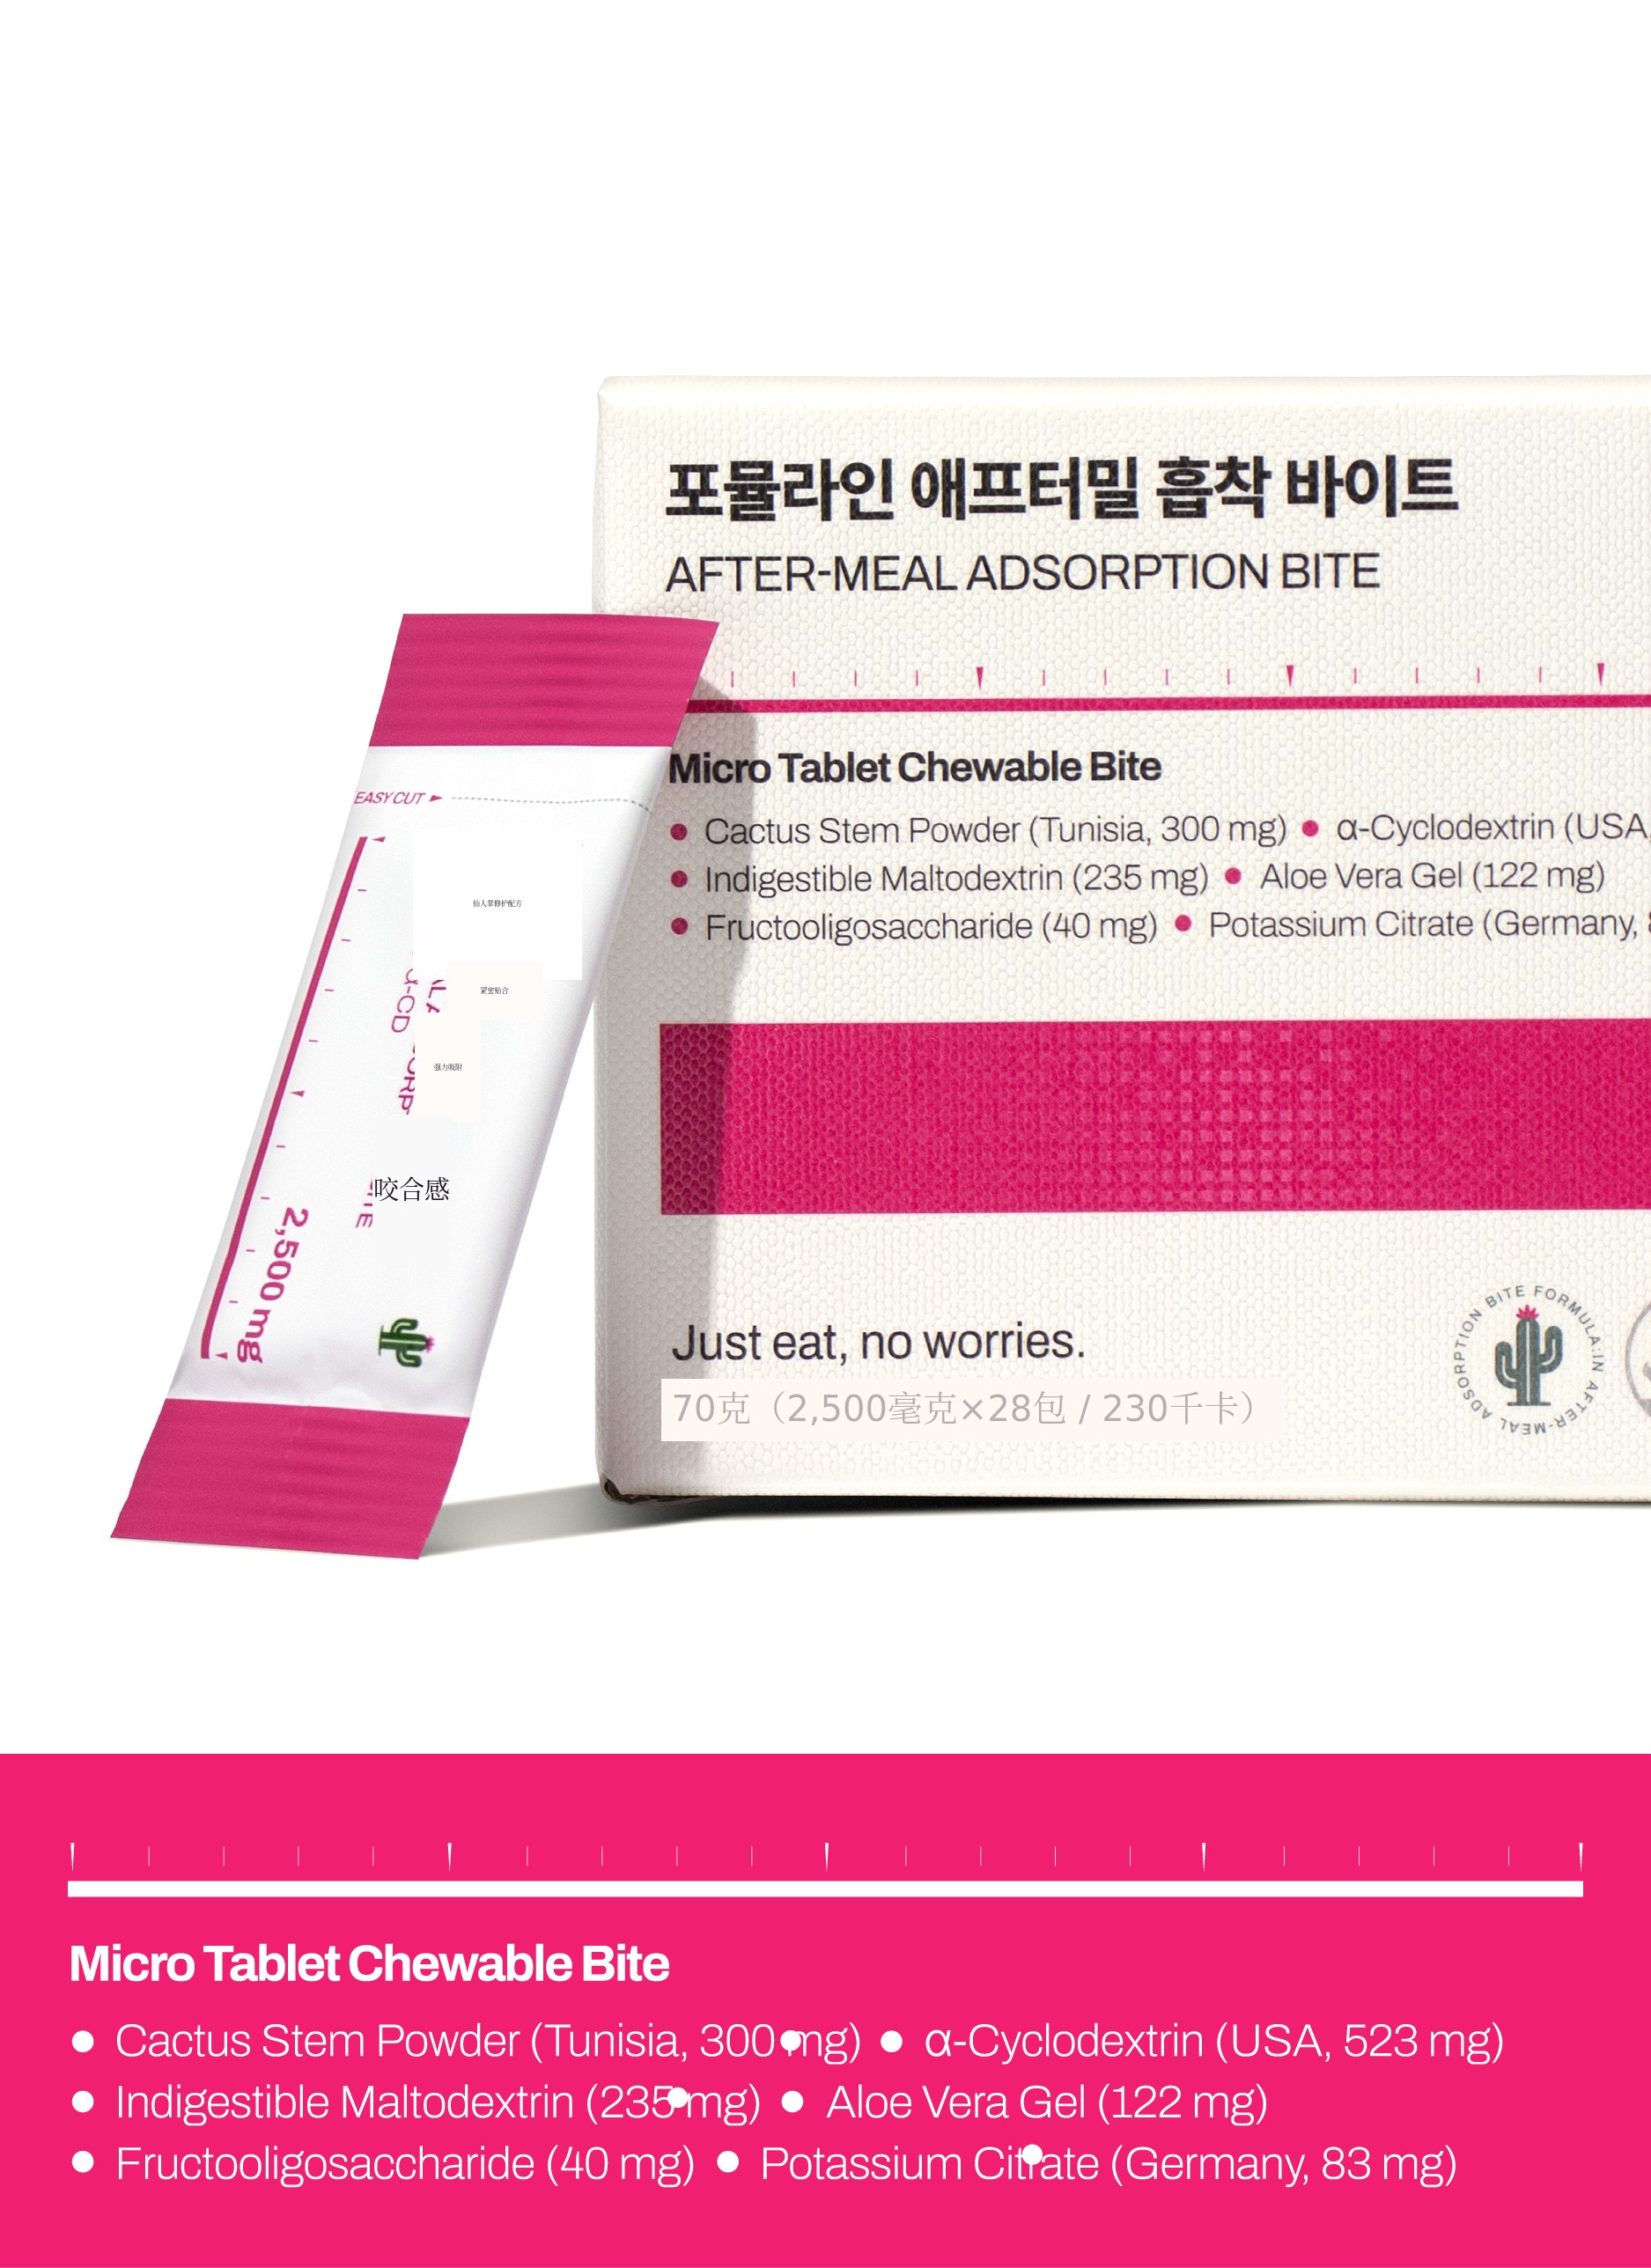

就这样诞生了‘Formuline吸附咀嚼片’。“有没有缺少的成分?”“味道还可以吗?”“无论何时何地都能方便食用吗?”我不断自问并改进。如果不能亲自感受到效果,绝不会上市。经过24次样品测试,终于完成了真正带来变化的组合。

Formuline的Formula完全不同。

Formuline 就是 从这个 问题 开始的品牌。

健康的 公式(Formula)装入 其中(In) 向顾客 传递 是 我们的目标。